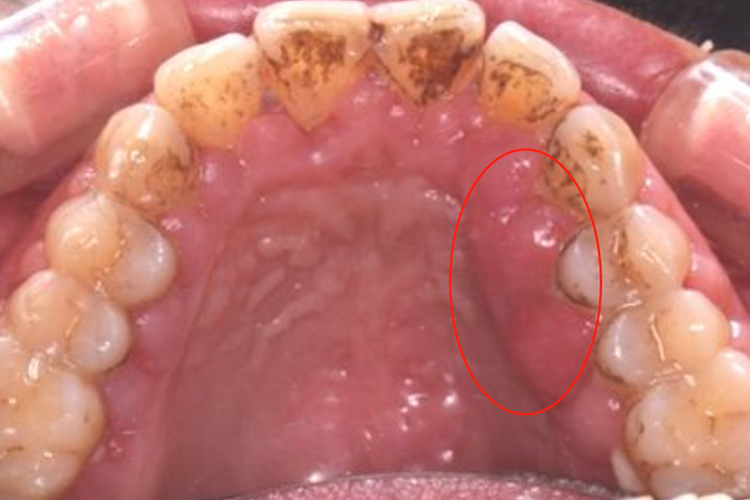

浆细胞龈炎:本病主要发生于牙龈,可侵犯多个牙齿或上下颌同时受累。牙龈鲜红、肿大、松软易破,表面似半透明状,有时如肉芽组织状,表面呈结节状或分叶状。极易出血,常并发不同程度的感染,有溢脓、口臭。

药物性牙龈增生:可呈球状、结节状或桑葚状突起于牙龈表面,向边缘扩展,覆盖部分牙面,像长了一个小肉芽一样。严重者妨碍进食。牙龈呈淡粉红色,质地坚硬,略有弹性,一般不易出血。无自觉症状,无疼痛。

牙龈瘤:通常呈圆形、椭圆形,有时呈分叶状。大小不一,从数毫米至1-2厘米,看着像长了一个小肉芽,质地较软、色红,一般无痛,肿物表面发生溃疡时可自觉疼痛。